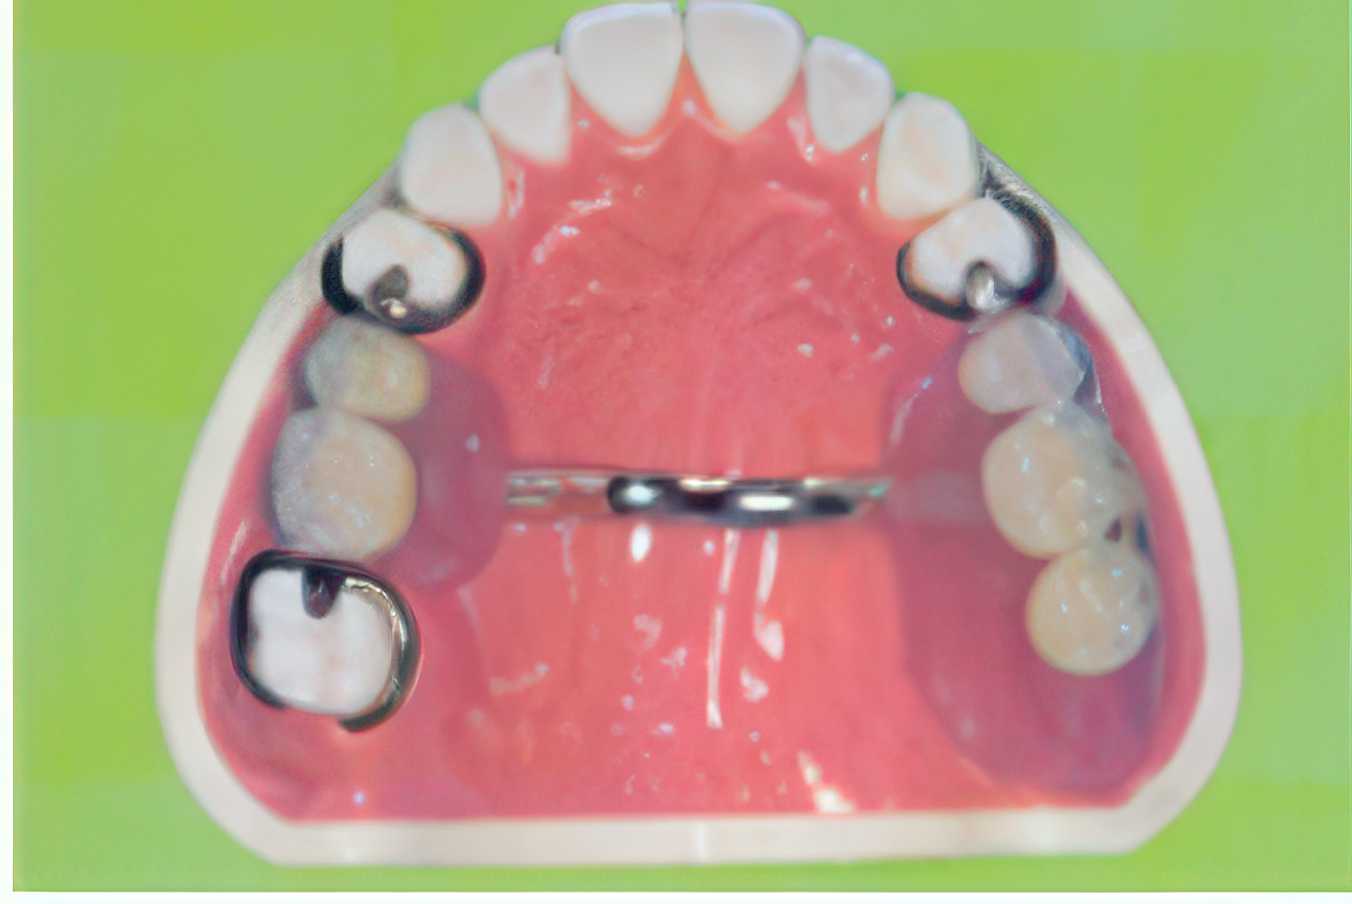

パーシャルデンチャーの症例

義歯には患者様の状態に応じて多様な種類があり、保険診療の範囲内で対応できるため、経済的な負担を軽減することが可能です。歯を失った際に義歯で補う方法として、毎日着脱して手入れを行う取り外し式義歯と、セメントで固定して取り外しの必要がない固定式義歯があります。どちらも健康保険適用の範囲で治療が可能で、従来から用いられてきた信頼性の高い治療法です。

取り外し式の部分入れ歯は、両隣の歯にバネをかけて安定を図るタイプが一般的です。また、ブリッジは欠損部の両側の歯を削り被せ物で補強し、失われた部分を人工歯で補填する方法であり、固定式義歯の一例です。クラウンなどの差し歯を装着する際には、歯の根の部分にコア(土台)を作ります。この土台は義歯の耐久性に関わる重要な部分であり、強固な土台であれば義歯の交換も可能です。しかし、コアが不安定で無理に外そうとすると歯の破損や抜歯が必要になる場合もあるため、素材選びは慎重に行う必要があります。

また、義歯治療においては、隣接する歯に負担がかかることも課題です。バネや削合による影響で虫歯や歯周病のリスクが高まることもあります。このようなケースには、インプラント治療を検討することも一つの選択肢です。インプラントはすべての部位に適応するわけではありませんが、さまざまな部位で対応が可能です。